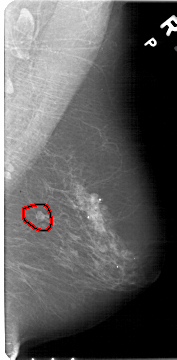

FILE: A_1457_1.RIGHT_MLO.OVERLAY

TOTAL_ABNORMALITIES 1

ABNORMALITY 1

LESION_TYPE MASS SHAPE LOBULATED MARGINS CIRCUMSCRIBED

ASSESSMENT 4

SUBTLETY 4

PATHOLOGY BENIGN

TOTAL_OUTLINES 1

BOUNDARY